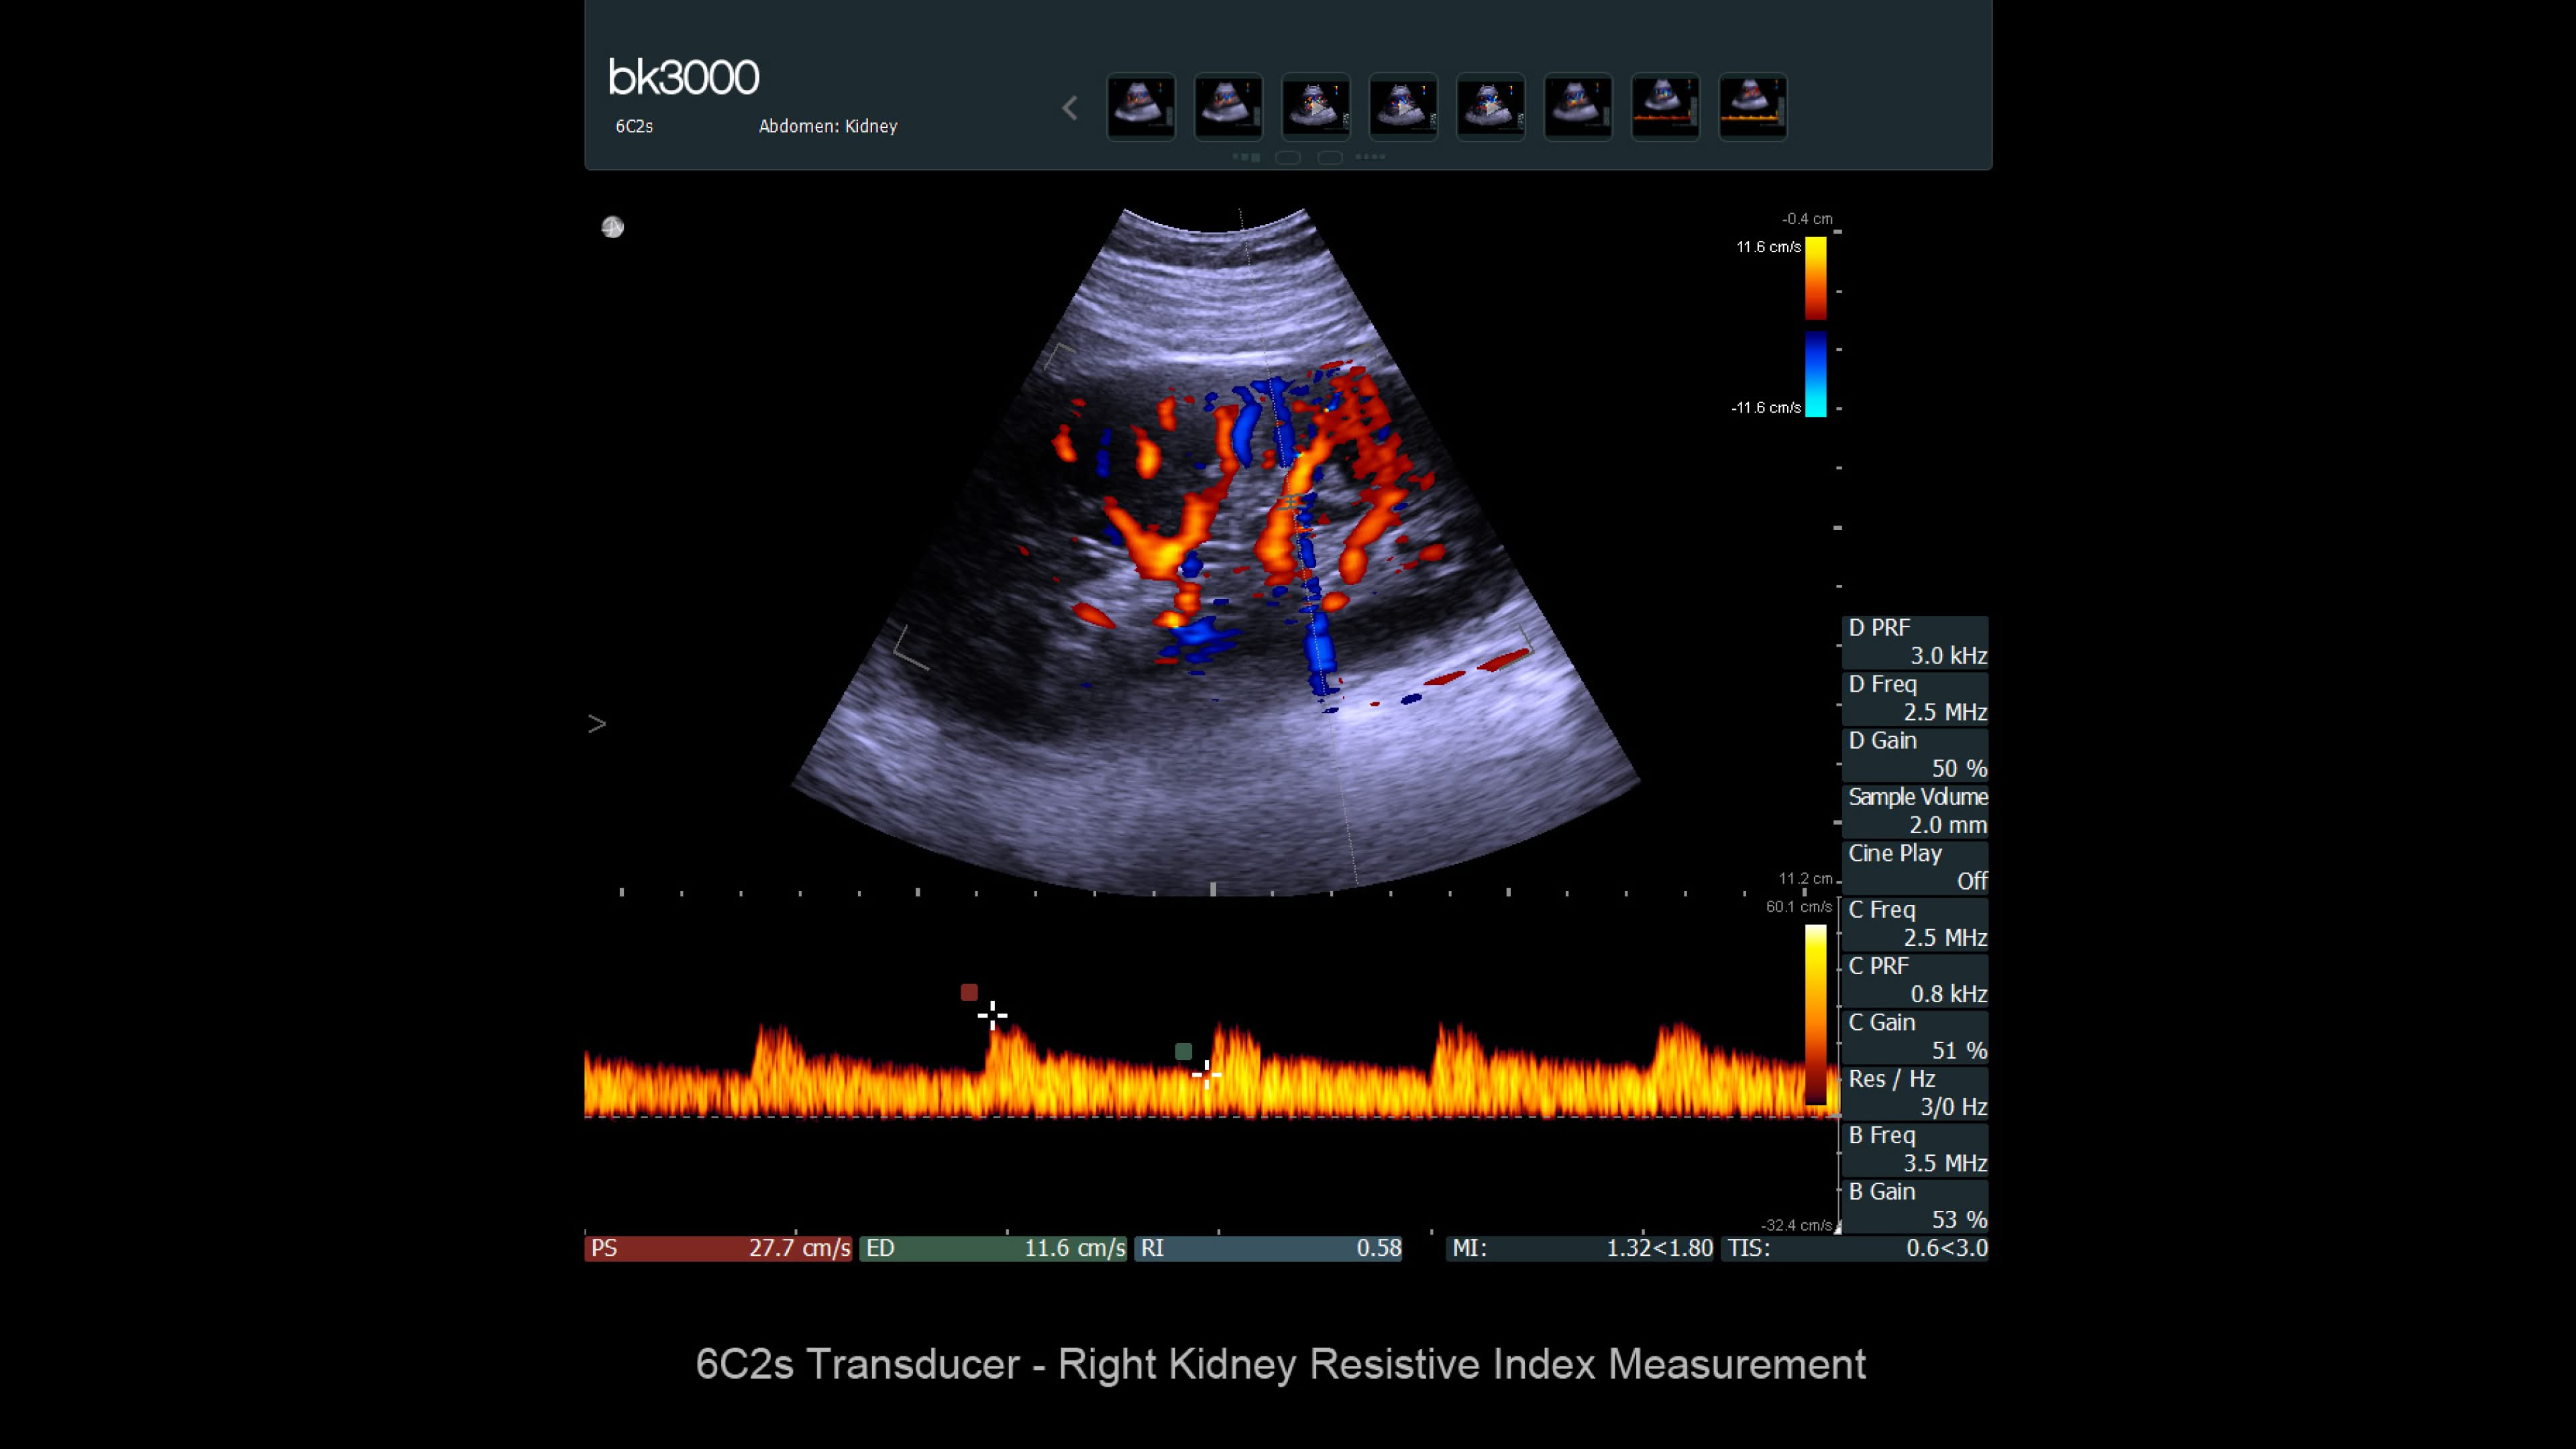

Ultrasound provides detailed information for kidney imaging, measurement, and biopsies. The bk3000 and bkSpecto systems help visualize fine anatomical details, see vascularization, measure blood flow, and locate kidney stones. The bkActiv, our flagship system, offers next-level imaging for prostate, renal, kidney, and bladder imaging, with sensitive Doppler for blood flow. Combined with sterilizable transducers, the bkActiv sets a new standard for surgical urology.

bk3000 ultrasound system

Discover the bk3000 ultrasound: high-resolution imaging for urology, colorectal, and pelvic floor care with advanced 3D and triplane precision.